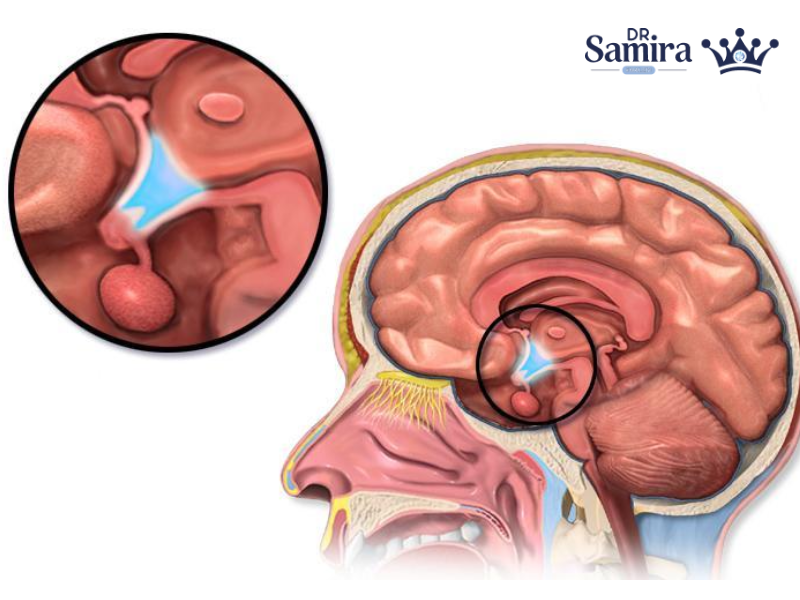

انواع آدنوم هیپوفیز موضوعی مهم در غدد درونریز و نورولوژی است، چون این تومورها با اینکه...